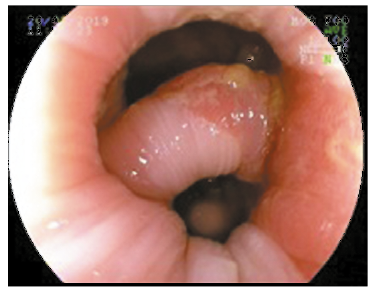

Al tacto rectal, se palpa puente transversal a nivel de recto bajo próximo al canal anal, de consistencia fibro-elástica, que divide la luz en dos hemicircunferencias. La mucosa rectal presentaba lesiones polipoideas blandas y móviles.

Se realizó videocolonoscopía, observándose a nivel de recto bajo próximo a canal anal puente mucoso de 10 mm de grosor que dificultaba el pasaje del endoscopio (Figuras 1 y 2).